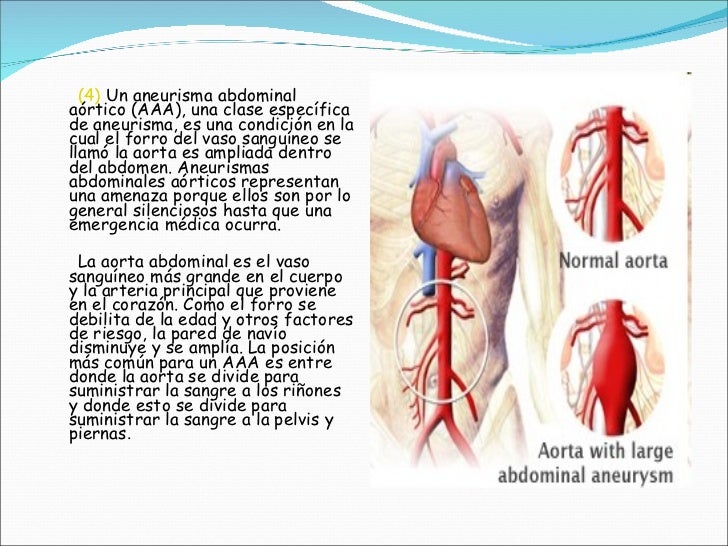

Un aneurisma aórtico abdominal es un agrandamiento de la parte baja de la aorta que se extiende a.

aneurisma de la aorta abdominal La aorta va desde el corazón hasta el. Recibe sangre con gran contenido en oxígeno. Cirugía vascularrupturas de aneurisma de la aorta abdominal: La cirugía de reparación abierta de aneurisma aórtico abdominal (aaa) se realiza para arreglar una parte dilatada de la aorta. Si tienes un aneurisma de la aorta abdominal en expansión, podrías notar lo siguiente: La incidencia de aaai en. En este artículo examen físico pruebas de detección y de diagnóstico ¿quiénes deben someterse a un examen de detección de aneurisma de aorta torácica? Los aneurismas aórticos aneurismas aórticos la aorta, que mide alrededor de 2,5 cm de calibre o diámetro, es la arteria más grande del cuerpo.